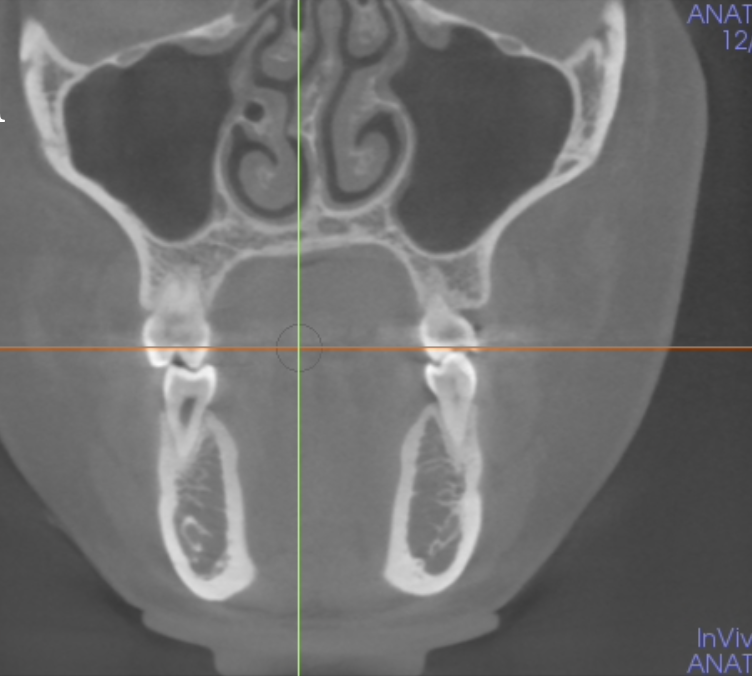

10

Coronal

11

Sagittal